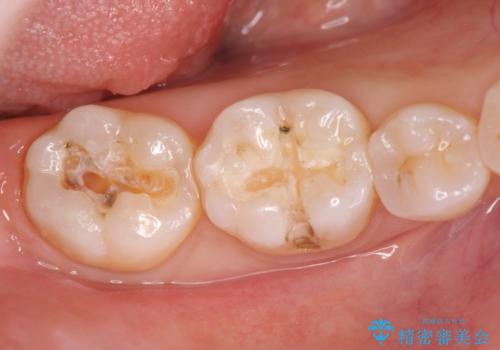

- 笑った時に見える銀歯を外したいと希望され来院されました。

銀歯の下には初期の虫歯も見られたので、除去後精密なシリコン印象を行いセラミックインレーを製作しました。